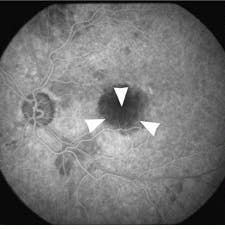

The minimally invasive PhotoPoint procedure can be performed in an office setting and requires no anesthesia. Patients are given peripheral injections of Purlytin, which then accumulates in the abnormal vessels under the macula. Fifteen minutes later, the drug is activated at the site with a precise application of laser energy through the pupil. Results of the treatment of the first 28 patients showed that eyes receiving the shorter duration of light exposure did better in both higher- and lower-drug-dosage groups. At optimal doses, patients experienced improvements in visual acuity at day one, with continued improvement through week 12. Fluorescein angiograms showed dramatic closure of the neovascular membrane in patients with choroidal neovascularization, according to Edgar Thomas, MD, director of retinal research at Cedars-Sinai Hospital (Los Angeles, CA) and one of the clinical investigators (see Figs. 1 and 2)."We think there is a variety in the degree of leakage within the membrane`s blood vessels," Thomas says. "We believe the treatment occludes the leakier blood vessels in the membrane." Although recurrence of leakage was detected in the PhotoPoint-treated area during the 12-week clinical-trial followup, this leakage did not affect the stabilization or improvement of visual acuity resulting from the treatment, he adds.